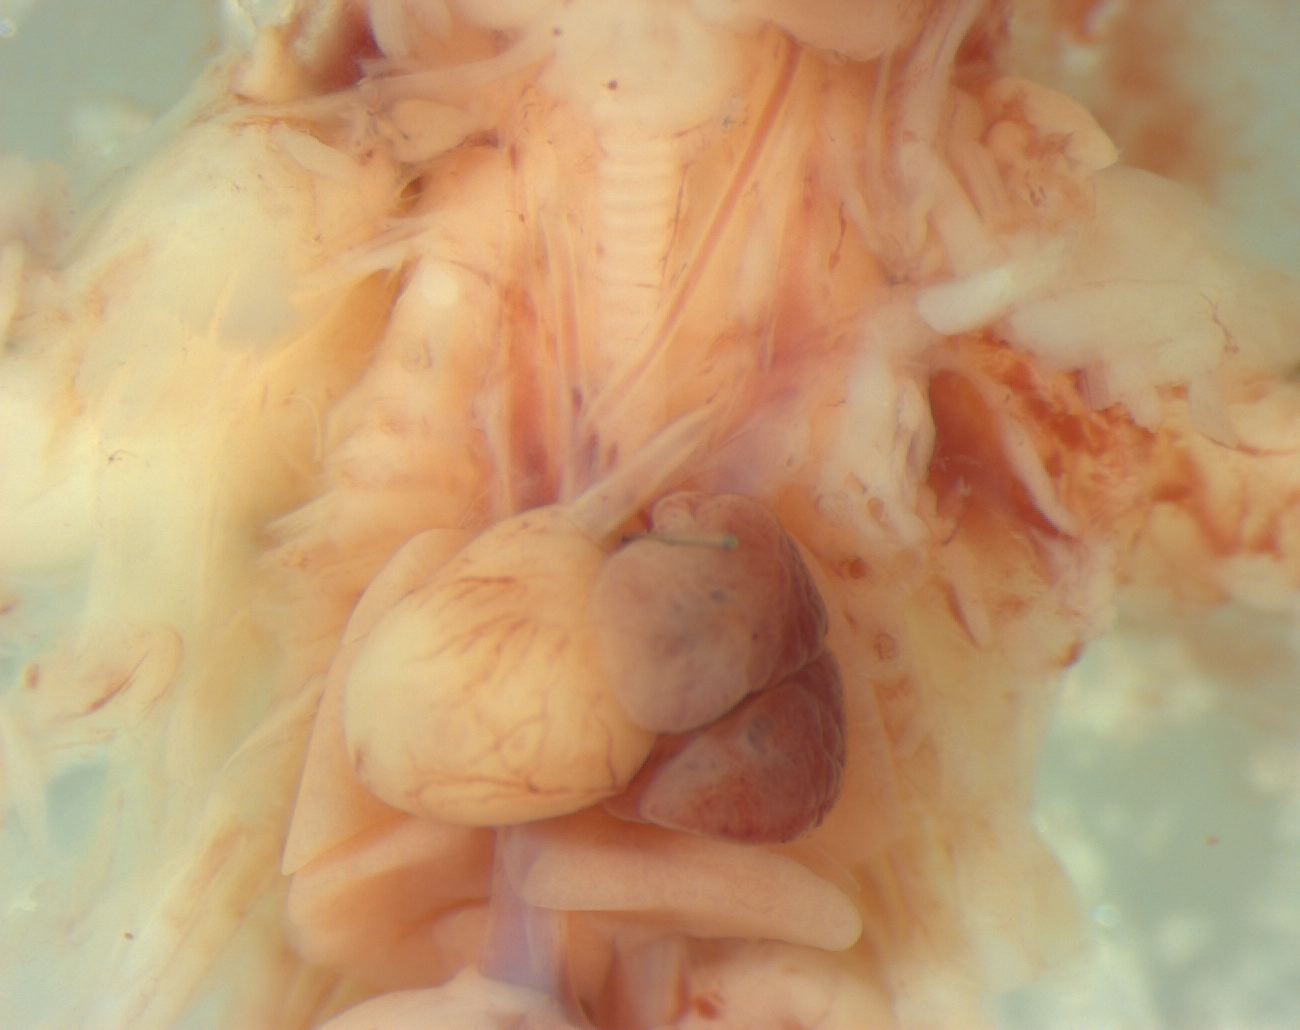

Caption Mutant 1200-003-NA shows dextroversion {S,D,S} with vascular ring

Copyright This image is from the Laboratory of Dr. Cecilia Lo, a member of the Cardiovascular Development Consortium (CvDC), Bench to Bassinet (B2B) program of the National Heart Lung and Blood Institute (NHLBI), and is displayed with the permission of the authors. J:175213